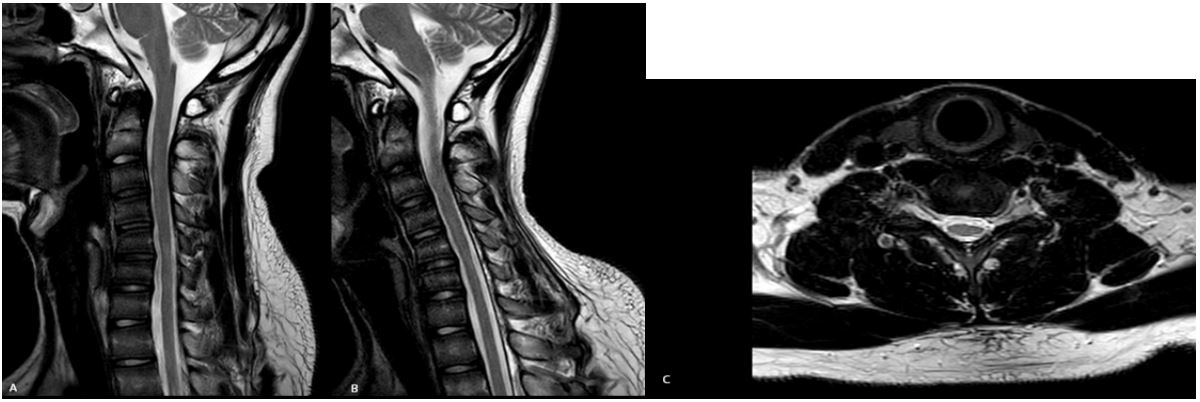

MRI in a neutral cervical position revealed the loss of normal cervical lordosis and an antero-posterior flattening of the spinal cord between C5 and C6. In MRI of cervical flexion, it showed anterior displacement of the posterior dura and high signal intensity between C5 and C6 (Figure 2). In his electrophysiological examination, nerve conduction velocities were normal but it showed attenuation of CMAPs of bilateral ulnar nerve. In needle electromyography, the denervation of the atrophied muscles was notable.

Figure 2: Local abnormal signals in the spinal cord (A); Cord flattening with loss of attachment of dura from subjacent lamina (B); Asymmetric cord flattening on neutral transverse T2WI (C).